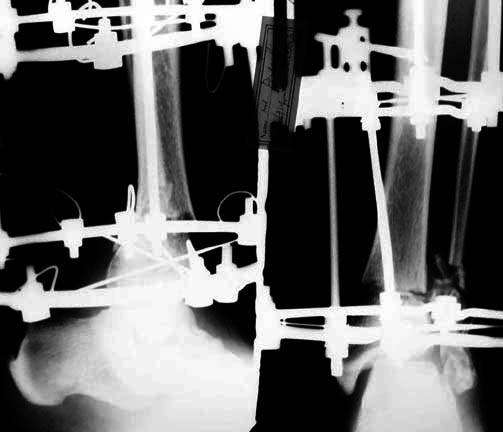

Middle aged adult was injured while travelling in a train(accidentally put his leg out). Presented with injury to left lower leg. Lacerated wound over the fibular fracture. Also another wound over the foot anterolaterally. No deficits.

On day one wound debridement followed by calcaneal traction done. Needs further stabilisation and a small split graft laterally. At present the fragments are putting pressure on the anterior skin. Will be happy to get your opinion on possible methods of stabilisation.

Day 1

Traction